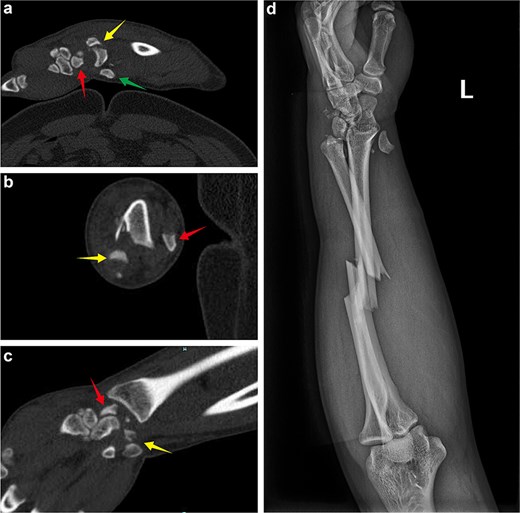

A 45-year-old manual worker presented following a fall from a scaffold about 2 m high. On examination, significant swelling of the left forearm and wrist was noted, with the disappearance of arterial pulsation and pallor of the hand. The patient also reported progressive paresthesia in the left hand, and motor weakness was observed. Emergency X-ray and wrist computed tomography (CT) scans revealed fractures of the ulna and radius, a dorsal fracture of the distal radius with dislocation of the inferior radioulnar joint, and dorsal dislocation of the lunate bone. Additionally, a scaphoid fracture, partially displaced toward the volar side was noted, along with a concomitant triquetrum fracture (Fig. 1). An emergency wound debridement and decompression procedure was performed. During the surgical intervention, a lazy S-shaped incision, ~25.0 cm in length, was made on the left palm and the palmar side of the forearm. Fasciotomy was conducted to release the deep fascia (Fig. 2). Intraoperatively, the wrist joint capsule was found to be damaged, exposing a scaphoid fracture that had fragmented into two pieces, with one fragment displaced toward the volar side. Additionally, the triquetrum bone was fractured into two pieces, with one fragment displaced toward the radius (Fig. 2). Following fracture reduction, the volar fragment of the scaphoid fracture was fixed in conjunction with the triquetrum fracture fragment using two Kirschner wires. The radial-carpal joint was also stabilized with two K-wires. Postoperative X-ray images revealed a poor reduction of the fracture ends, while the position of the lunate bone was generally considered acceptable (Fig. 3).

(a and b) After the first operation, X-ray images revealed that the volar displaced scaphoid fracture end had been incorrectly fixed to triquetrum fracture end. Temporary fixation of the unstable wrist joint was achieved using Kirschner wires, while the ulna and radius were not fixed. The lunate bone had not yet been completely repositioned.